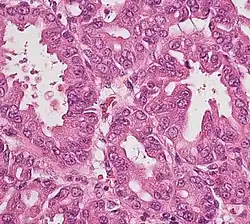

Histopathology

The most common form of pancreatic cancer (adenocarcinoma) is typically characterized by moderately to poorly differentiated glandular structures on microscopic examination. There is typically considerable desmoplasia or formation of a dense fibrous stroma or structural tissue consisting of a range of cell types (including myofibroblasts, macrophages, lymphocytes and mast cells) and deposited material (such as type I collagen and hyaluronic acid). This creates a tumor microenvironment that is short of blood vessels (hypovascular) and so of oxygen (tumor hypoxia).[2] It is thought that this prevents many chemotherapy drugs from reaching the tumor, as one factor making the cancer especially hard to treat.[2][3]

| Cancer type | Relative incidence[11] | Microscopy findings[11] | Micrograph | Immunohistochemistry markers[11] | Genetic alterations[11] |

| Pancreatic ductal adenocarcinoma (PDAC) | 90% | Glands and desmoplasia | ![]() |